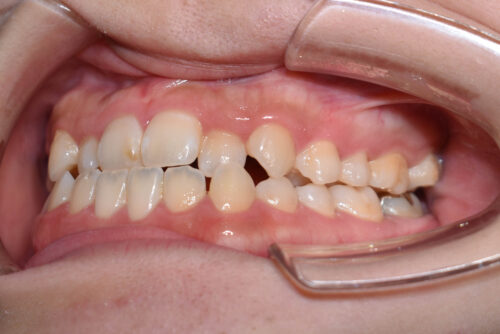

上下とも歯が唇側に傾斜し

下の歯が上の歯よりも外にでている 受け口の状態でした。

ワイヤー8か月後です。

本症例のように

歯科矯正用アンカースクリュー(デュアル・トップオートスクリュー)を利用し

下顎の後方移動を行うことで

歯を抜かない非抜歯矯正治療でも

受け口を整えることができます。